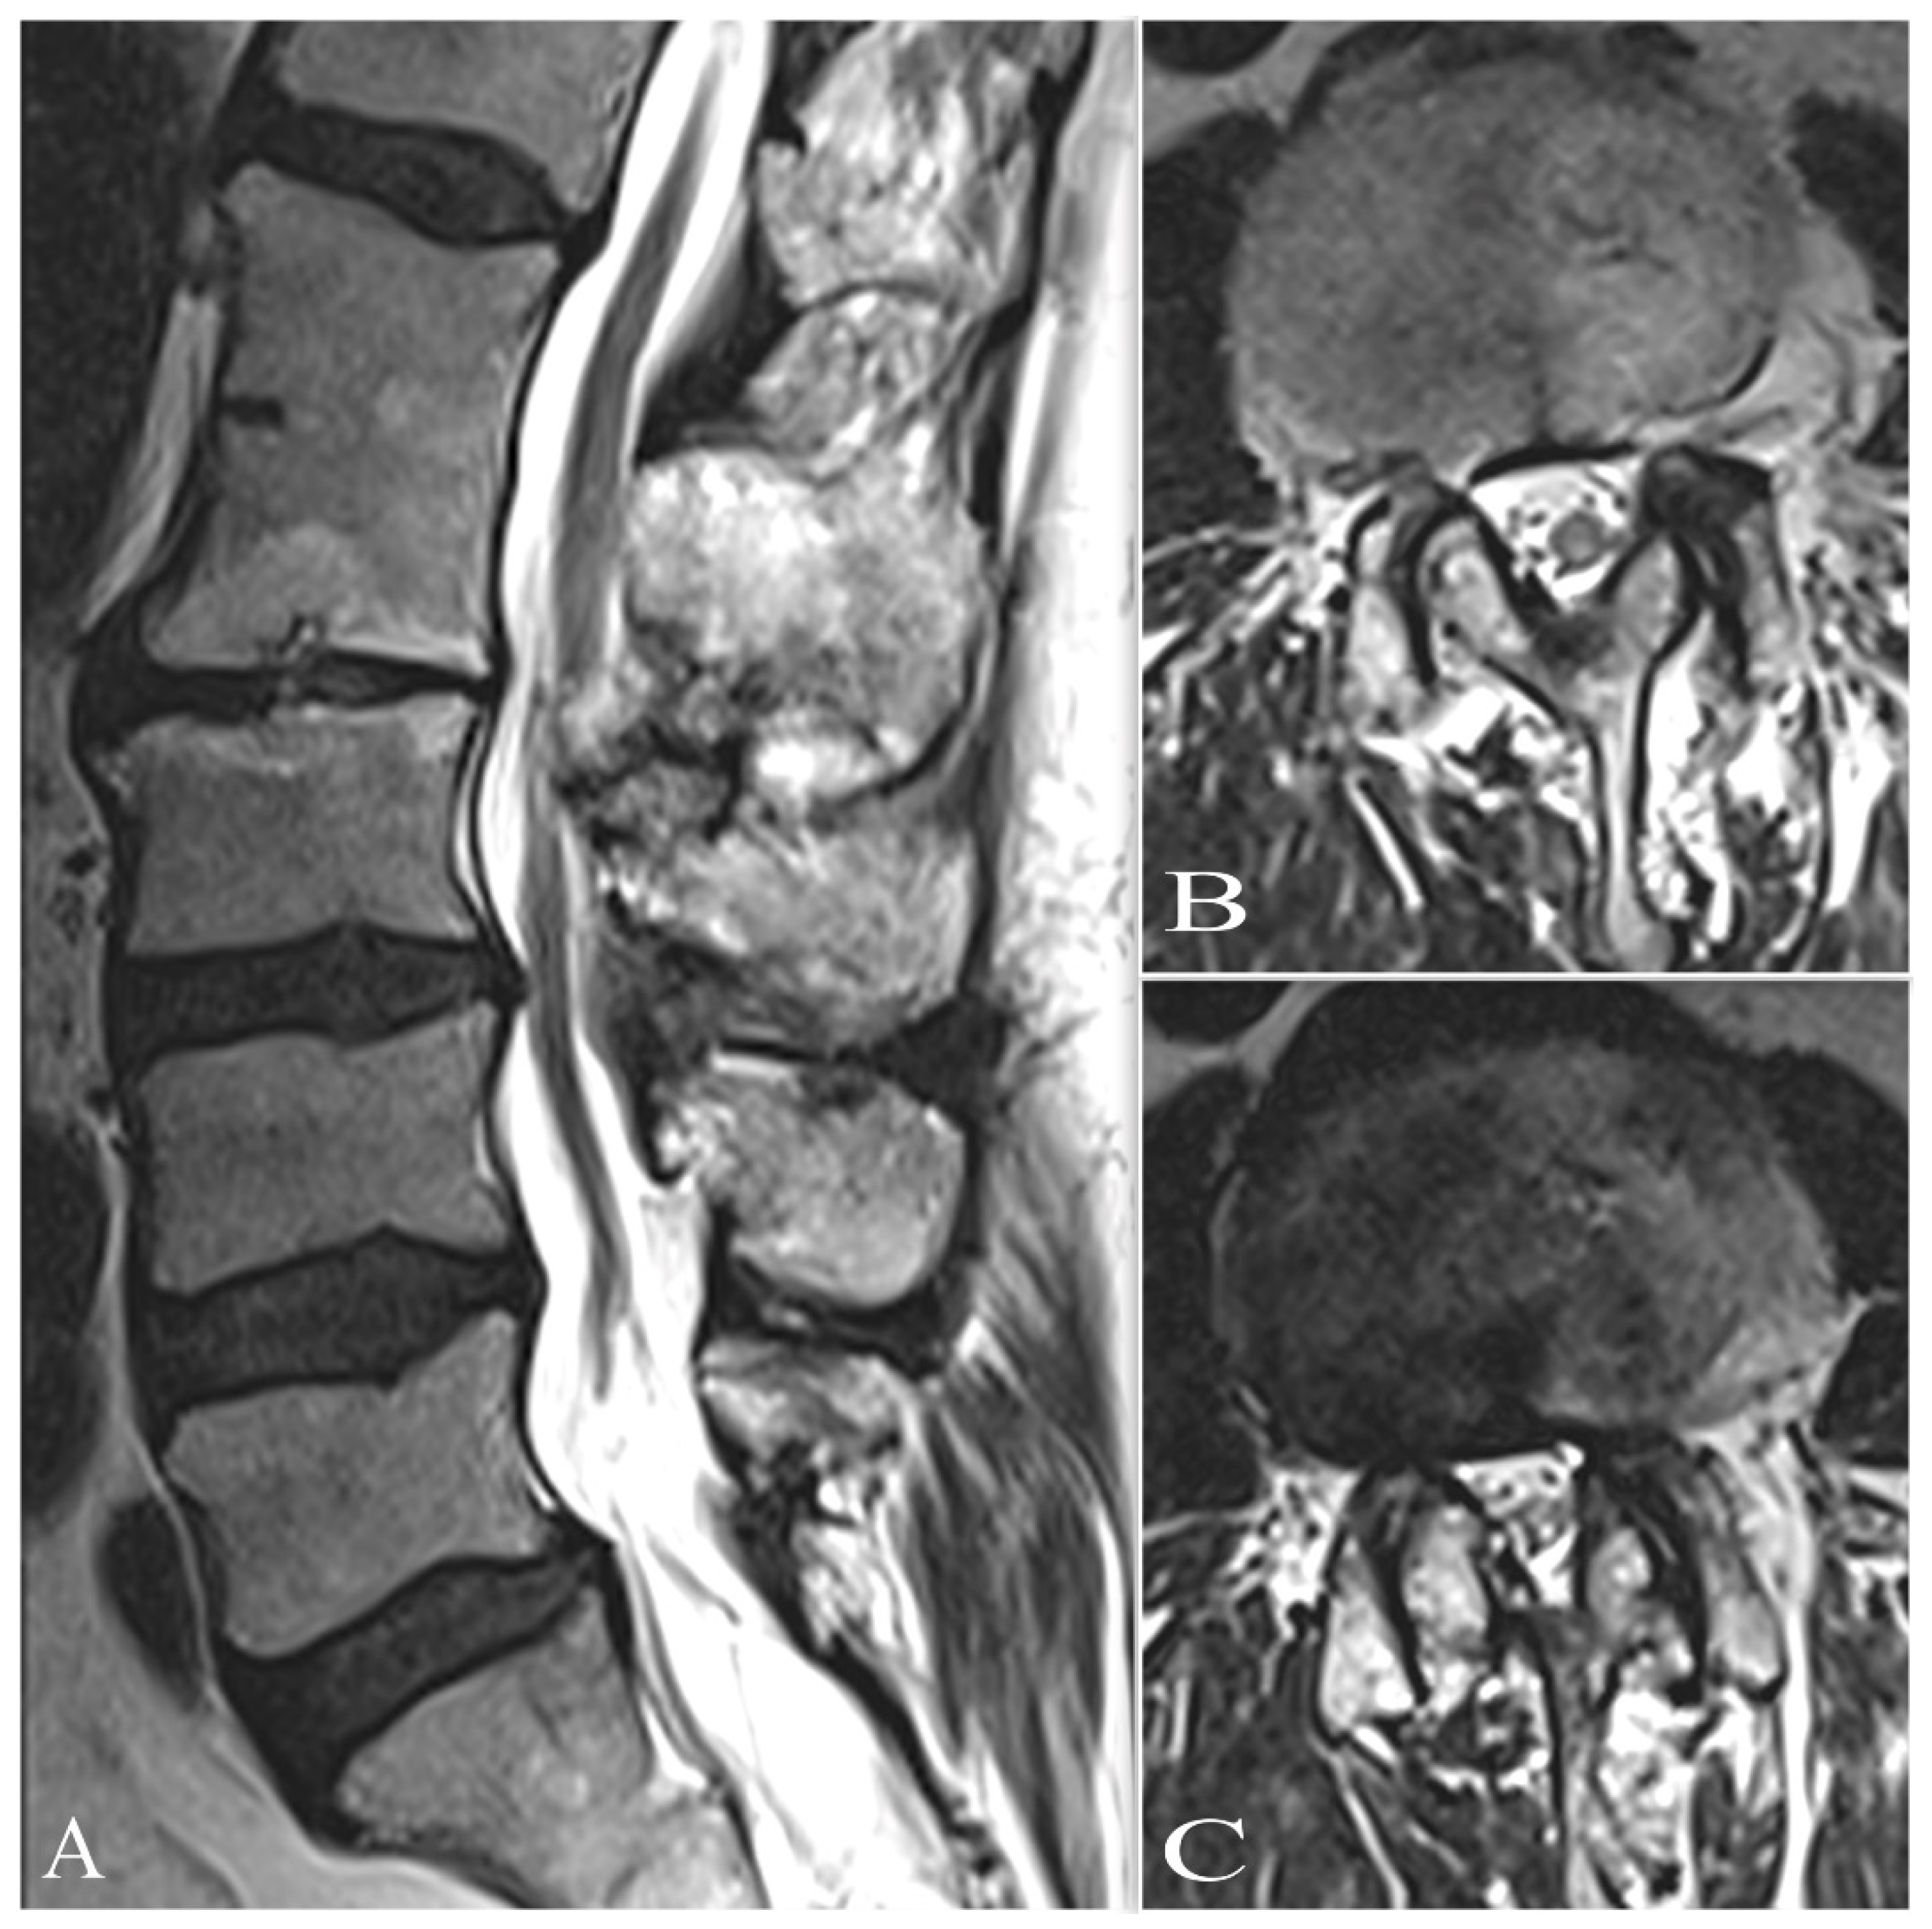

| MRI (n = 50) |

| Segmental widening and swelling of spinal cord |

| Ring-enhancing margin (abscess) |

| Cystic lesion with ring enhancement |

| CSF flow obstruction |